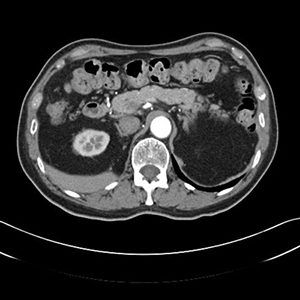

CT abdomen

Poate identifica chisturi, abcese, infecţii, inflamaţii, tumori sau anevrisme, noduli limfatici, corpuri străine, hemoragii, diverticulită, boală inflamatorie intestinală, apendicită, traumatisme etc. Se vizualizează ficatul, pancreasul, splina, intestinele, sistemul urinar, artera aortă.

- ficatul: tomografia computerizată poate descoperi la acest nivel tumori, hemoragii şi alte afectiuni hepatice;

- pancreasul: poate identifica tumori şi inflamaţii ale pancreasului;

- vezica biliară şi căile biliare principale;

- glandele suprarenale: prin tomografie computerizata se pot identifica tumori sau creşterea în volum a glandelor;

- splina: identificarea leziunilor traumatice ale splinei sau determinarea dimensiunilor acesteia.